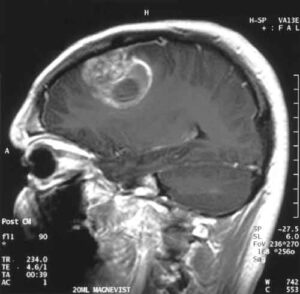

Glioblastoma: una molecola offre ottimi risultati nel trattamento del tumore

Una semplice molecola, simile strutturalmente all'aceto, sembra funzionare nel trattamento del glioblastoma, un tumore del cervello. (altro…)

La molecola nasce dalla combinazione tra il cisplatino, un comune farmaco antitumorale, e un altro composto, il dicloroacetato (DCA), che...